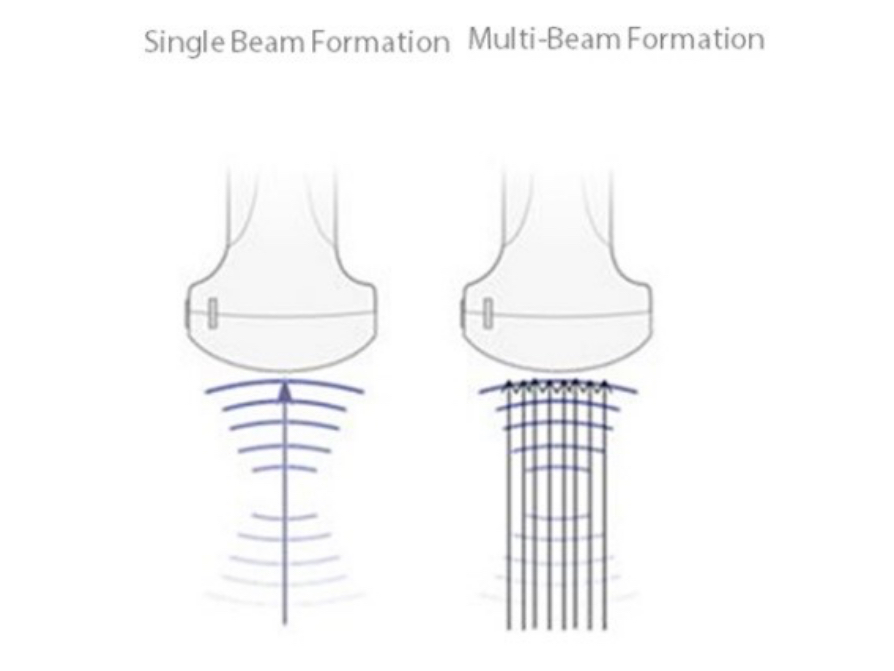

Maximum 8 times tasking for one transmitted beam, resulting in excellent time resolution and higher frame rate.